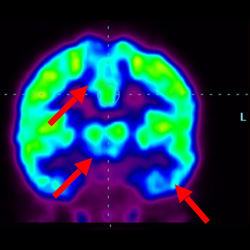

腦癱細胞療法, 腦癱治療

細胞治療前 PET CT 掃描顯示神經(jīng)組織中的藍/黑色區域,表明腦癱引起的大腦損傷。

細胞治療后,藍色和黑色區域減少,并且看到更活躍的區域。這表明損傷減少并改善了大腦功能。